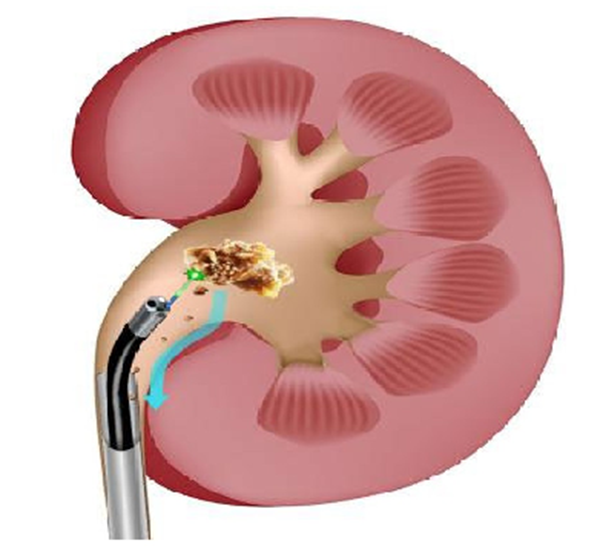

模式圖

(負(fù)壓吸引,邊碎邊吸,高效清石)

徐州市中醫(yī)院泌尿外科鄭典寶主任團(tuán)隊(duì)經(jīng)過(guò)綜合考慮和術(shù)前精心準(zhǔn)備,為王女士實(shí)施在全麻下末端可彎曲負(fù)壓吸引鞘輸尿管軟鏡碎石取石手術(shù),運(yùn)用銩激光粉末化模式將結(jié)石擊碎成粉末,利用負(fù)壓吸引裝置聯(lián)合末端可彎曲負(fù)壓吸引鞘將結(jié)石粉末吸出體外。

這一術(shù)式可做到術(shù)中視野清晰,持續(xù)腎內(nèi)低壓,降低膿毒血癥概率,且術(shù)中即刻清除結(jié)石,結(jié)石殘留率低,因此縮短患者術(shù)后留置雙J管的時(shí)間,從而減輕了留置雙J管引發(fā)的各種不適(血尿、腰痛等),由此保證了手術(shù)的安全性及高效碎石清石。